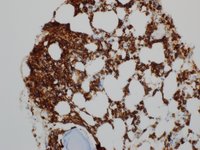

Lymphoplasmacytic Lymphoma CD138

Category: Lymphoma: Mature B-cell and Plasma cell Neoplasms > Low-grade B-cell lymphoma > Lymphoplasmacytic lymphoma

CD138 positive plasma cells are arranged singly and in small clusters. The background shows CD138 negative hematopoetic cells.